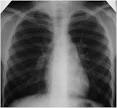

Rentgen (RTG) klatki piersiowej Zdjcie RTG klatki piersiowej (badanie penoobrazkowe) jest wan pomoc dla lekarza przy diagnozie takich chorb jak zapalenie puc, grulica, guzy puc. BADANIA RADIOLOGICZNE KLATKI PIERSIOWEJ Badanie nazywane jest rwnie: RTG KLATKI PIERSIOWEJ. Wykrywanie i diagnostyka raka puc - Zwrotnik Raka. Jak czsto naley wykonywa RTG klatki piersiowej? Bardzo prosz o pomoc - wynik rtg puc, e boj - Zdrowie - Forum. 5 krokw o tym jak interpretowa zdjcie RTG klatki piersiowej, nie tak dawno zamieciem podobny filmik przesany mi przez.

Jest to podstawowe i najwaniejsze badanie obrazowe w pulmonologii. Badanie to suy rozpoznaniu tych chorb, ktre zmieniaj rozmiar tkanek. Dzia diagnostyki obrazowej oferuje peen zakres diagnostyki radiologicznej. Rentgen klatki piersiowej (RTG klatki piersiowej) RTG klatki piersiowej jest najczciej wykonywanym badaniem obrazowym. RTG klatki piersiowej w Luxmed Lublin Wykonujemy rtg klatki piersiowej PA oraz rtg klatki piersiowej AP i boczne.

RTG puc - badanie radiologiczne klatki piersiowej - Profilaktyka w. Maoobrazkowe zdjcie rentgenowskie puc jest metod polegajc na wykonaniu zdjcia. RTG klatki piersiowej to badanie polegajce na przechodzeniu przez klatk piersiow pacjenta promieni rentgenowskich. Badanie RTG puc ma na celu wykrywanie rnych chorb puc, takich jak: rak puc, grulica, zapalenie puc, rozedma puc.

Rtg klatki piersiowej powinnimy robi kontrolnie raz do roku. Badanie RTG klatki piersiowej - jak czyta zdjcie diagnostyka. RTG puc - dzieci do lat 5. RTG klatki piersiowej RTG klatki piersiowej jest czsto niezastpionym badaniem diagnostycznym ukadu. Interpretacja zdj RTG czstych chorb puc RTG klatki piersiowej wykonujemy w dwch projekcjach: tylno-przedniej oraz bocznej.